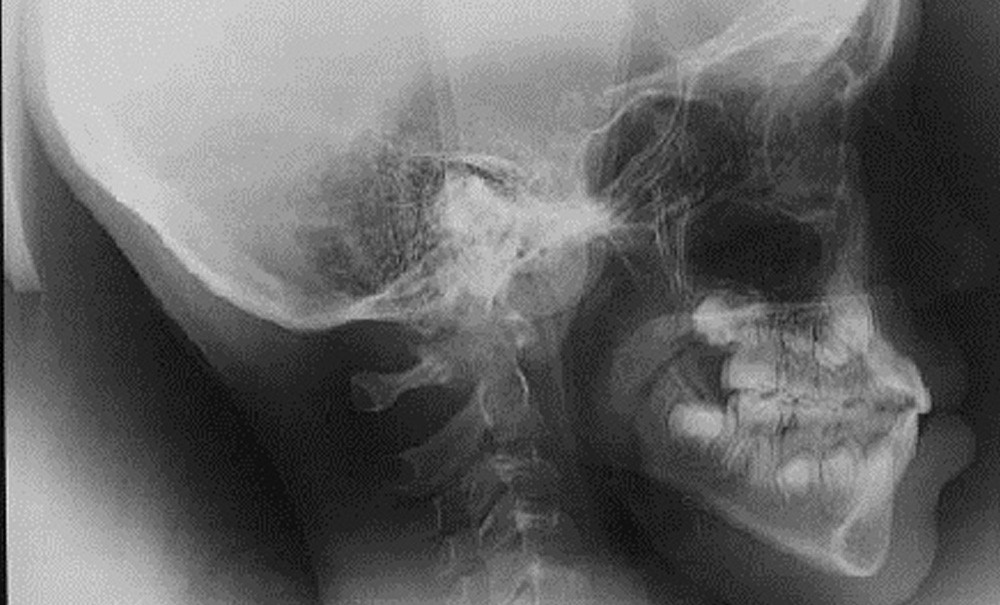

La bascule du plan d’occlusion est une anomalie pouvant être causée par des anomalies de posture ou des anomalies de mimiques, des anomalies squelettiques ou des anomalies alvéolo-dentaires. La gestion thérapeutique bénéficie de l’essor des ancrages osseux et des progrès de la chirurgie des contours mandibulaires.

On décrit souvent une bascule frontale qu’on oppose à une bascule horaire ou anti-horaire mais, dans une bascule, les trois dimensions sont généralement impliquées avec, chacune, une participation plus ou moins importante.

La bascule du plan d’occlusion peut être en relation avec la plagiocéphalie. L’ostéopathe Gianni Marangelli, qui a été expert pour la rédaction des recommandations de la HAS, invite à regarder la symétrie globale du patient.

Ces décalages sont le plus souvent situés à gauche, ce qui a peut-être un lien avec le fait que la plagiocéphalie touche préférentiellement le côté droit. La plagiocéphalie entraîne un décalage de position de la mandibule sans changement de forme ou une sorte de compensation avec dissymétrie de forme mandibulaire entraînant un indice de…